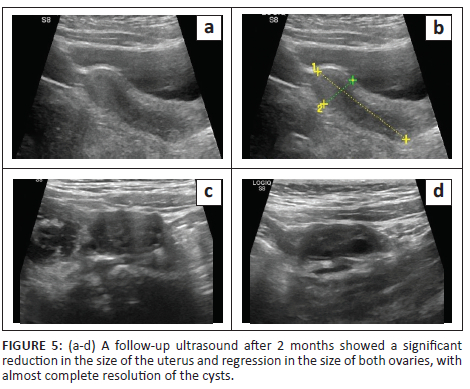

At follow-up after 2 months, the child showed significant improvement in clinical symptoms. There was a substantial reduction in weight, with marked improvement in appetite and constipation. Facial features also showed marked improvement. Ultrasound pelvis revealed a significant decrease in the size of the uterus, which measured 3.8 cm × 1.3 cm. Regression in the size of the ovaries was seen with the complete resolution of the cyst and follicle. The right ovary measured 2.2 cm × 1.5 cm and the left ovary measured 2 cm × 0.8 cm. (Figure 5)